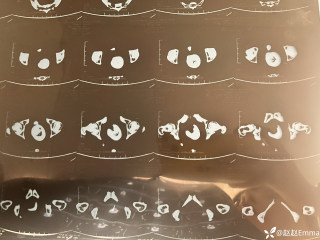

玩耍被撞后10岁男孩被诊断有肿瘤,多器官切除 当地卫健局:医院存在问题,已立案

2023年10月26日,来自山东菏泽市成武县的小烨和他家人的命运被彻底改变了。这个原本阳光、可爱的小男孩在一次意外被撞击后,在医院检查出了腹腔内存在肿瘤,并在手术中被切除了包括十二指肠、胰腺、大部分胃和小肠等多个器官。此后便无法再像正常人一样吃饭、喝水,活着要靠长期静脉注射营养液。一份2024年12月由第三方机构出具的司法鉴定意见书显示,当时给小烨做手术的成武县人民医院在该医疗行为中存在过错,与小烨的损害后果之间存在因果关系,建议医疗过错在损害后果中的原因力大小为同等原因。此外,另一份由成武县卫生健康局在2025年9月28日发出的书面答复中显示,成武县人民医院存在24小时内未完成病历;手术知情

目前知道的消息,第一,术前发现一个血肿,然后做增强CT发现一个占位,没说血肿与肿瘤的关系,术后病理没有描述肿瘤出现破裂出血,大概率就一个小血肿,我就不明白当地主任凭哪个指针去给这小孩开急诊刀的?哪个指南告诉他需要急诊开?第二,诊断不明确他想的不是进一步检查,一边观察一边进一步查,他反而选择腹腔镜探查,这个探查的指针在哪?第三,腹腔一个血肿,没有活动性出血,没有血压心率出现问题,为什么要开腹进去碰它?不能等血肿吸收再明确肿瘤性质吗?第四,1点进腹,3点病理结果出来,按这个时间还算顺利,应该还没出事,孩子还算平稳,病理是低度恶性,切了就治愈,他一年能开几台这手术,就敢继续做,拿孩子练手。第五,后面